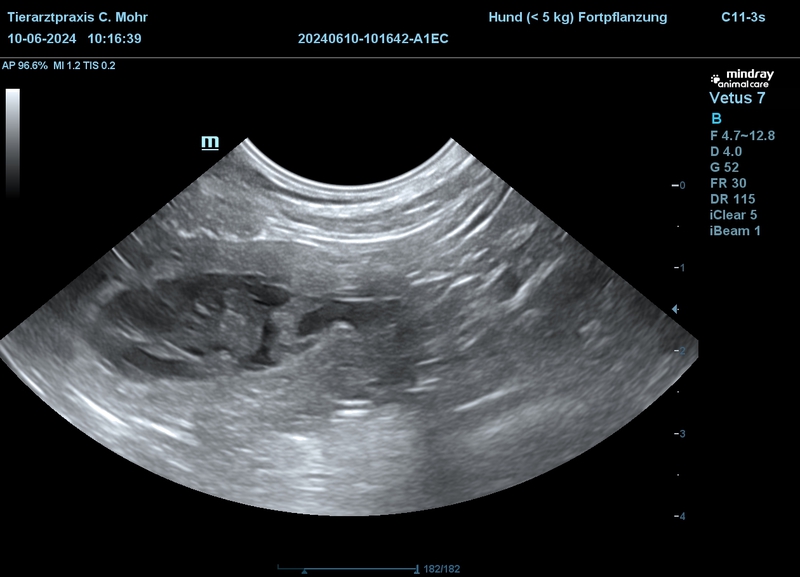

Gina hatte sich relativ schnell auf ihren Wurf vorbereitet und am Sonntag dem 14.07.2024 ihre Welpen problemlos zur Welt gebracht.